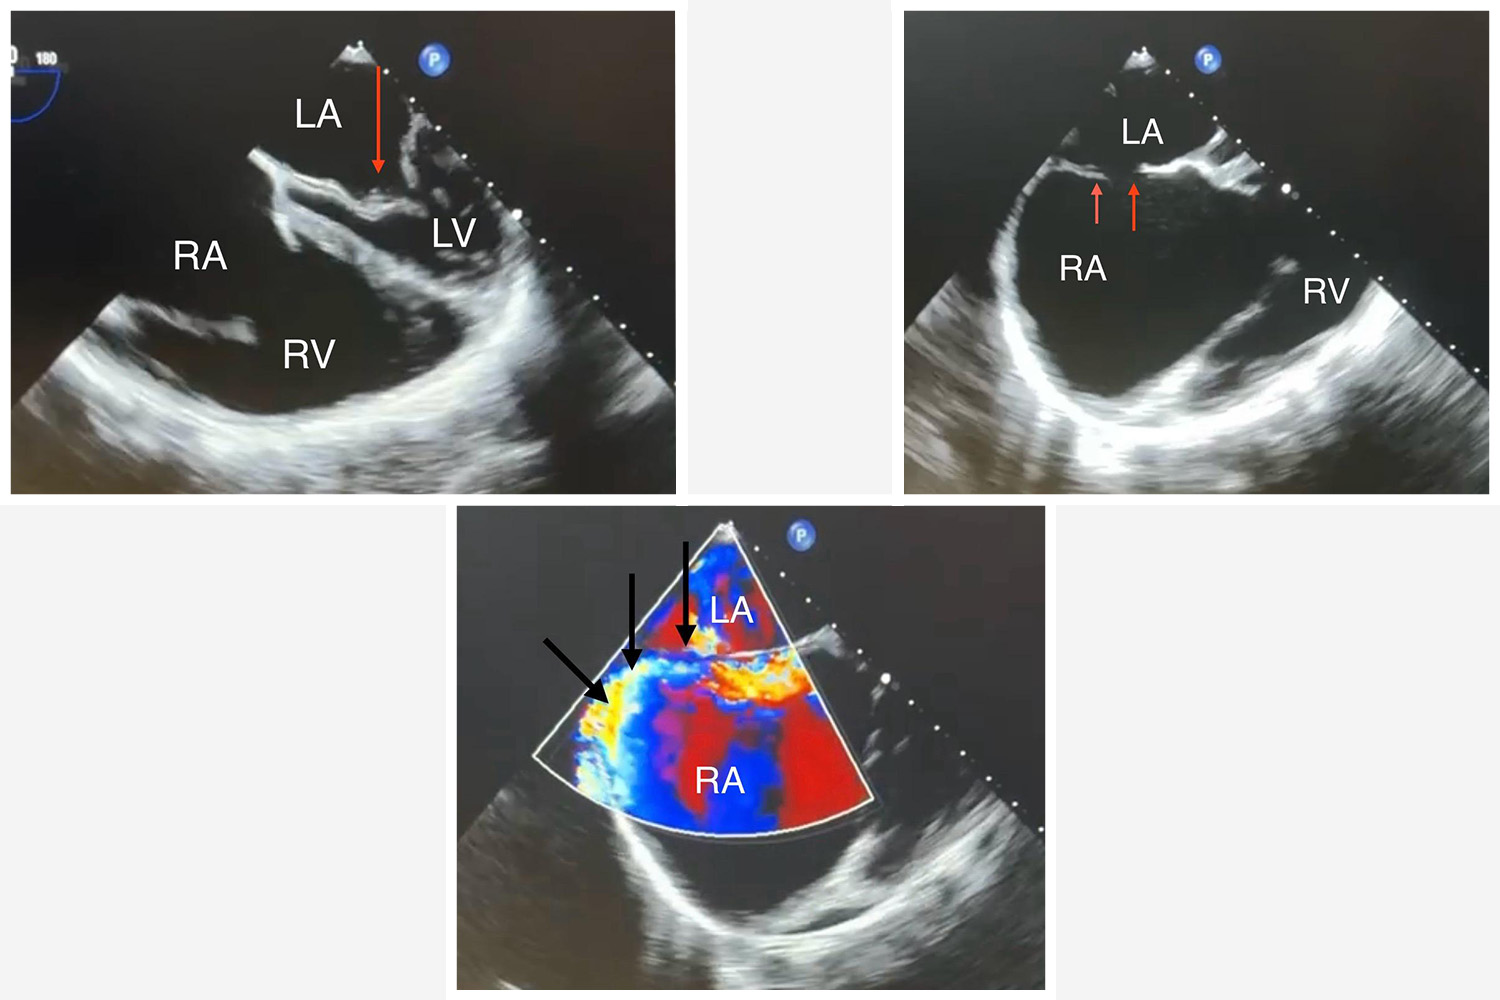

Image of the Week - 30 October 2024

Doctor Ossama Maadarani